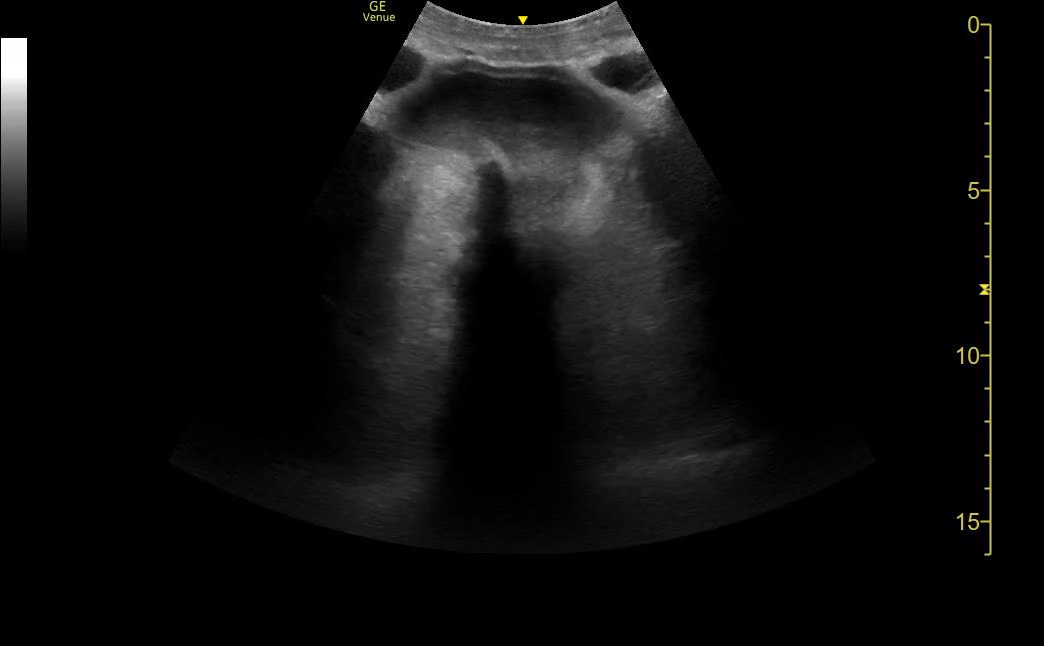

Too much depth

The problem with too much depth is that it wastes screen space. The machine has to use computing power to fill every pixel on the image. Every pixel that is used for something other than the AOI is wasted space. That means less of the screen is filled by the area of interest.